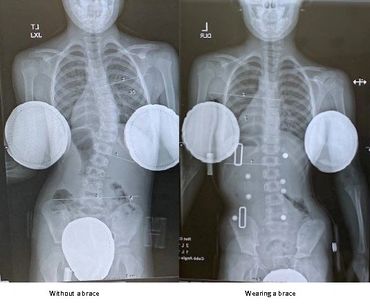

Our goal is to correct the spinal curves as much as possible while wearing the custom spinal brace. This is an example of curve correction while wearing a custom scoliosis brace from Chicago Pediatric Orthotics. The left x-ray is while wearing the TLSO and the right is without. Near 100% correction is noted.